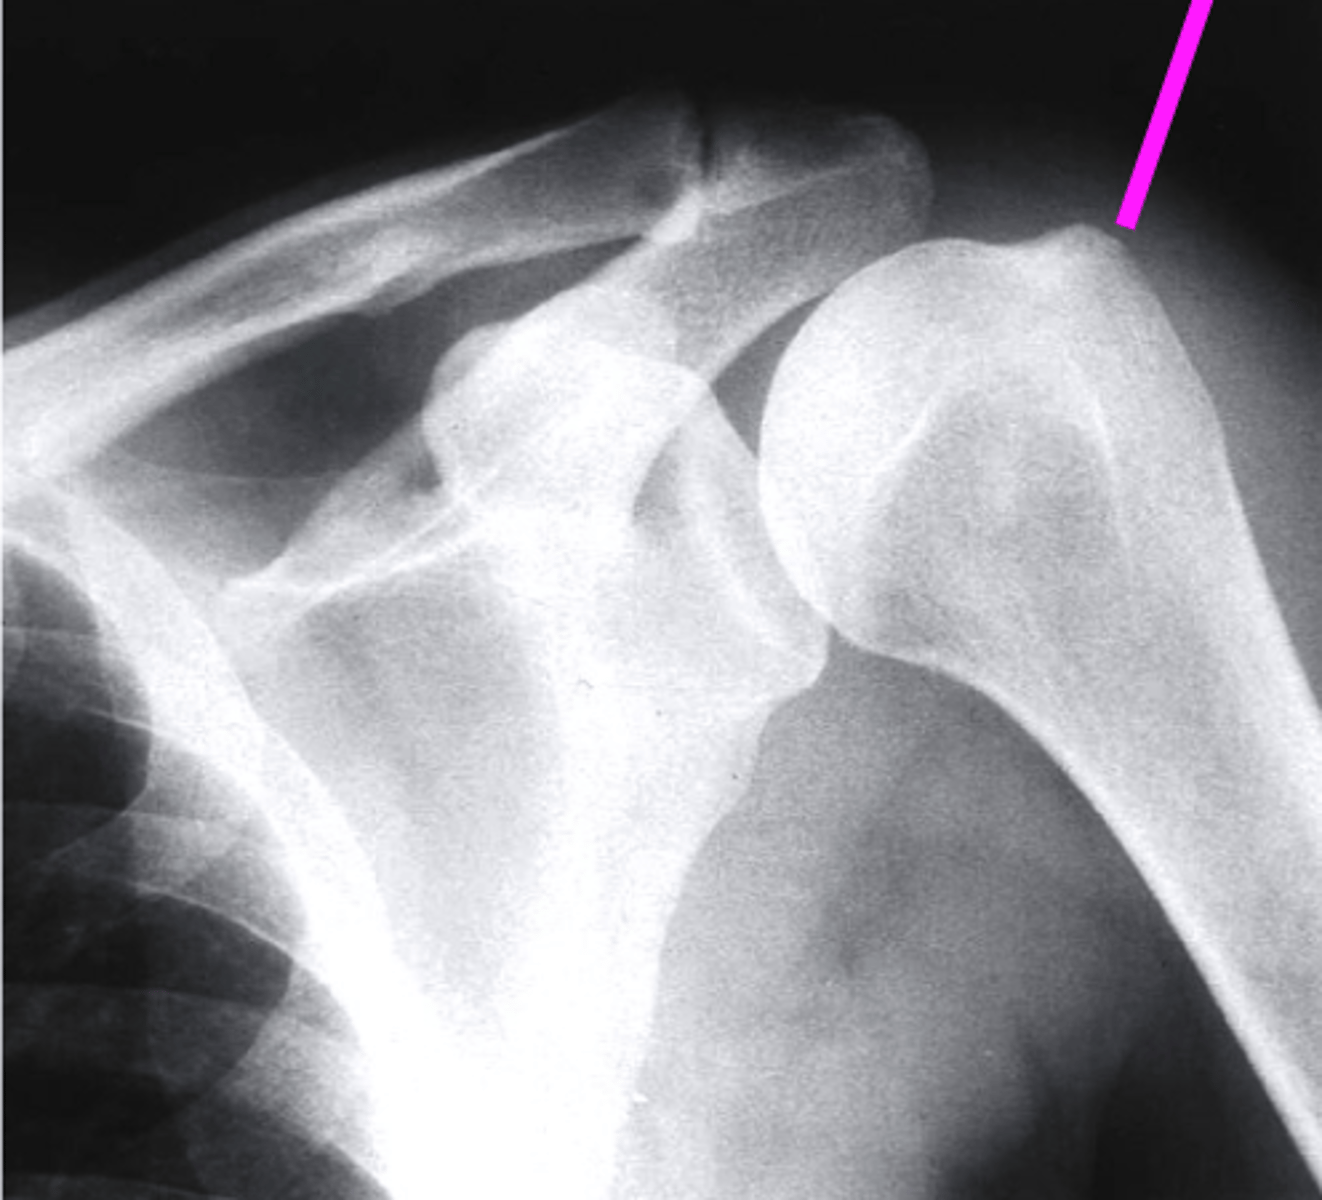

AP + IR

what view is this?

clavicle

what does the pink line point to?

spine of scapula

coracoid process

glenoid fossa of scapula

AC joint

acromion

Humeral Head

lesser tubercle